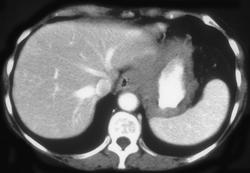

Gastric Leiomyoma